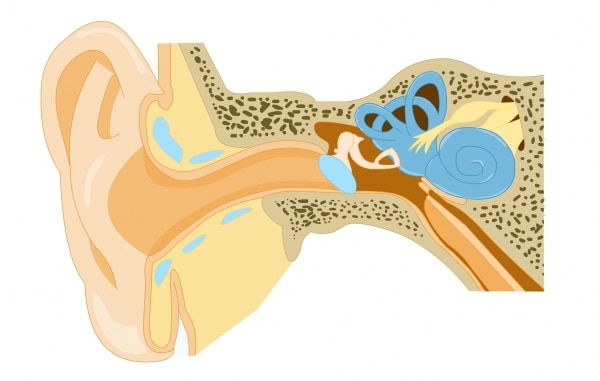

- La réalité virtuelle pour diagnostiquer les commotions cérébrales